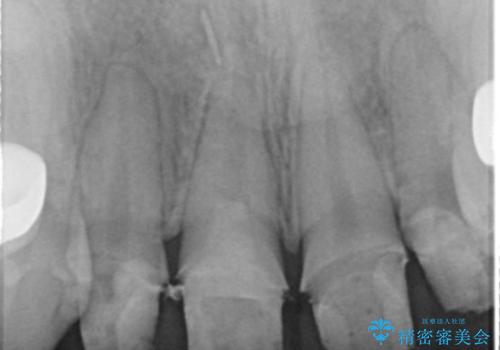

- 子供の頃にジュースが原因で虫歯が多発し、レジン修復をしていたが見た目の改善を希望され来院されました。

レジン充填・虫歯を丁寧に全て除去したのちジルコニアセラミックを用いた前歯の審美改善を計画します。